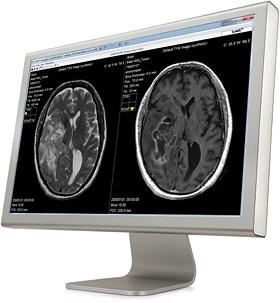

Image courtesy of SyntheticMR AB

June 2, 2015 — Cincinnati Children’s Hospital Medical Center (CCHMC) has evaluated synthetic magnetic resonance imaging (MRI) on pediatric cases to study and clinically validate its use on children. Results from the first part of the evaluation, which used SyMRI software, shows the synthetic images are diagnostically satisfactory in comparison with conventional sequences.

SyMRI IMAGE from SyntheticMR optimizes the MRI workflow and shortens scan time using synthetic MRI. This is achieved by a single MR quantification scan of 5-7 minutes. Based on this single scan, conventional standard T1W, T2W and FLAIR images and any other combination of TE, TR and TI can be shown without rescanning the patient, allowing a substantial reduction in examination time.